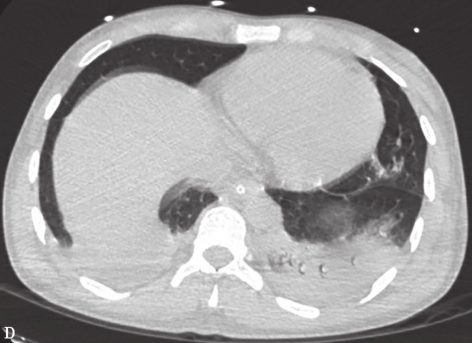

1小时条评论67岁男性,因间断发热1.5个月,咳嗽1个月余入院。2个余月前于墨西哥某第二次世界大战时期遗留坑道内进行地质勘探,坑道内遍布腐烂生物并有蝙蝠栖息。胸部CT示双肺多发结节斑片影、纵隔淋巴结肿大。既往身体健康。针对临床特点,应该鉴别哪些疾病? 一、入院疑诊 ...